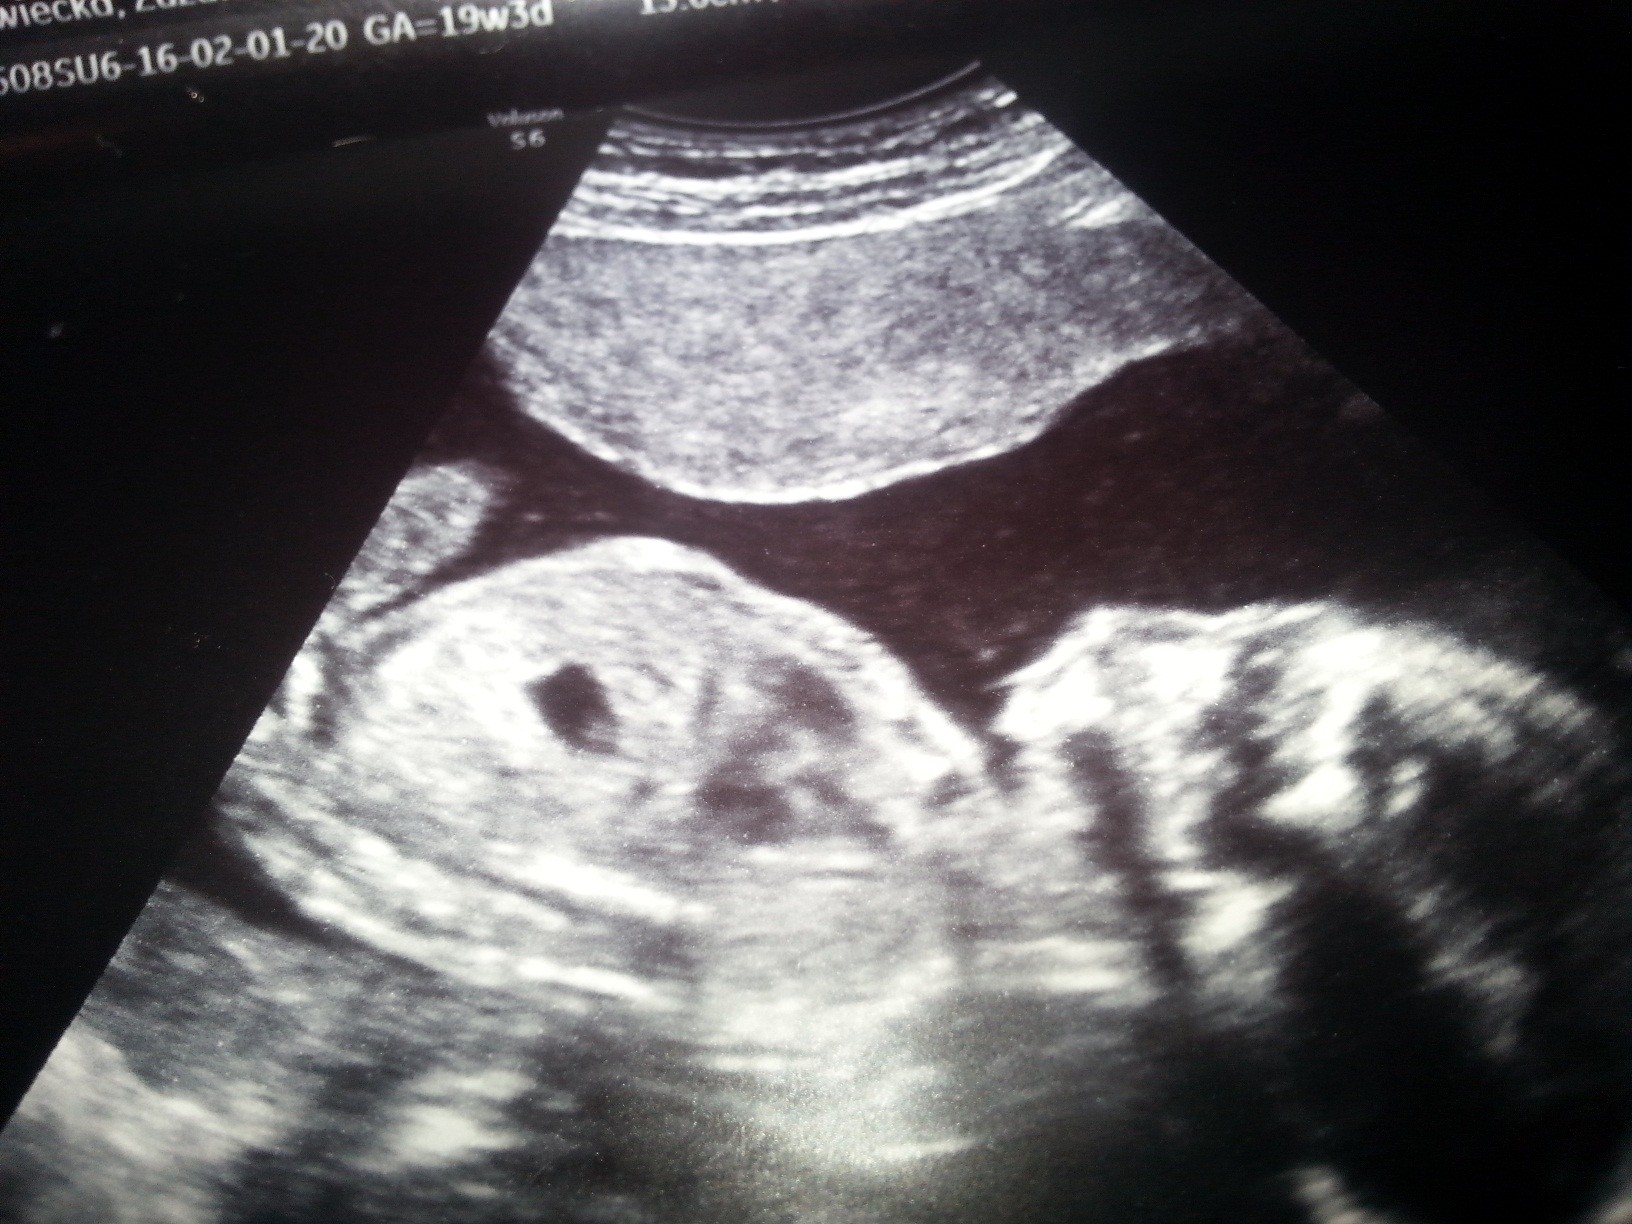

Hej:) Jestem po kolejnej wizycie i jeżeli chodzi o płeć usłyszałam od lekarza raczej DZIEWCZYNKA:-) :) eh teraz trzeba miesiąc czekać czy to się potwierdzi:hmm:

( Planowaliśmy dziewczynkę, ale raczej niewiele czynników spełniłam, nie traktowałam tego aż tak serio)

Załączniki

• 20160202_191035.jpg

20160202_191035.jpg

417 KB · Wyświetleń: 79

Suzi gratuluję dziewczynki :) w którym tc jesteś?